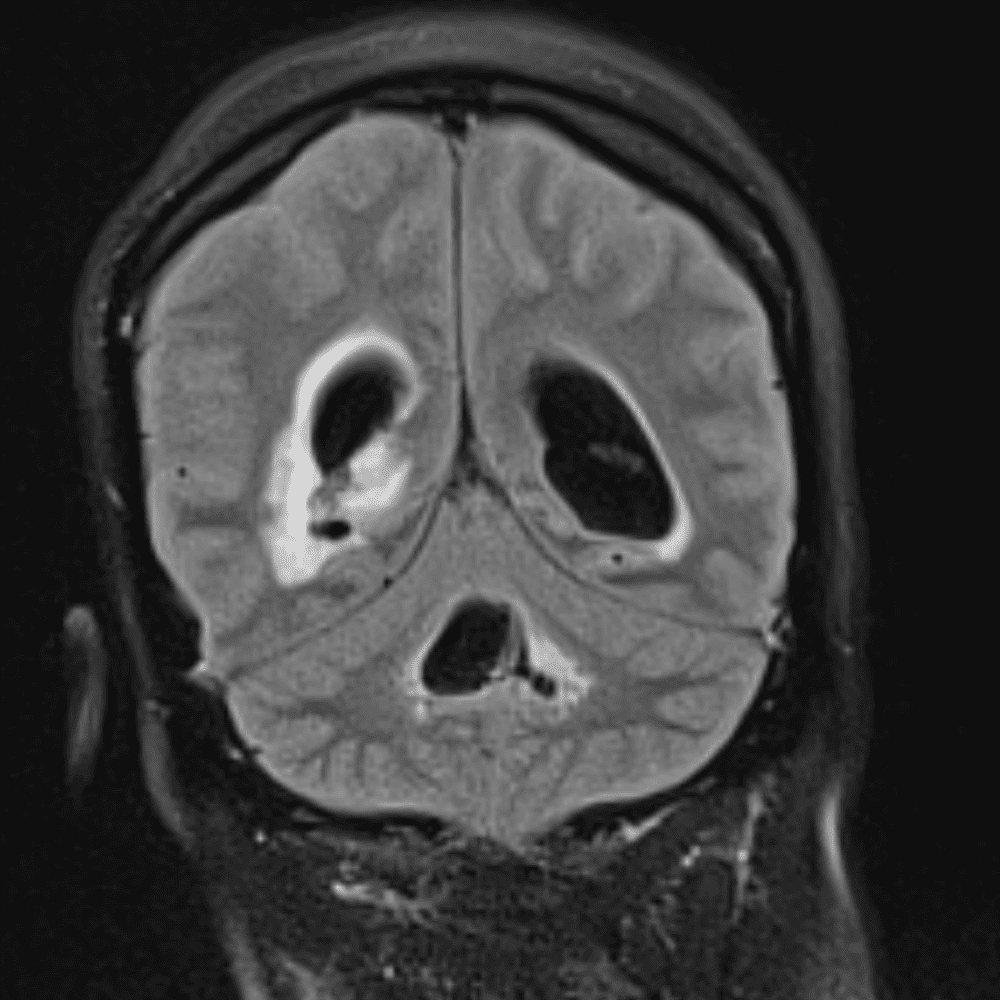

๋‹น์ง ์‹œ ํ”ํžˆ ๋ณผ ์ˆ˜ ์žˆ๋Š” ์‚ฌ๋ก€์˜ ์ „ํ˜•์ ์ธ ์˜ˆ๋ฅผ ํฌํ•จํ•ฉ๋‹ˆ๋‹ค.

39 ์‚ฌ๋ก€

์—ฐ์Šต

๋ฏธ๋ฌ˜ํ•˜๊ฑฐ๋‚˜ ์–ด๋ ค์šด ์‚ฌ๋ก€์™€ ์ผ๋ถ€ ์ •์ƒ ์‚ฌ๋ก€๋ฅผ ํฌํ•จํ•˜์—ฌ ๋‹น์ง์„ ์‹œ๋ฎฌ๋ ˆ์ด์…˜ํ•ฉ๋‹ˆ๋‹ค.

50 ์‚ฌ๋ก€